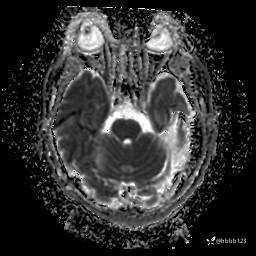

患者男,43岁。

简要病史:癫痫患者复诊,昨日发作5-6次,建议住院进一步治疗。

入院完善脑癫痫组合序列:

DWI: